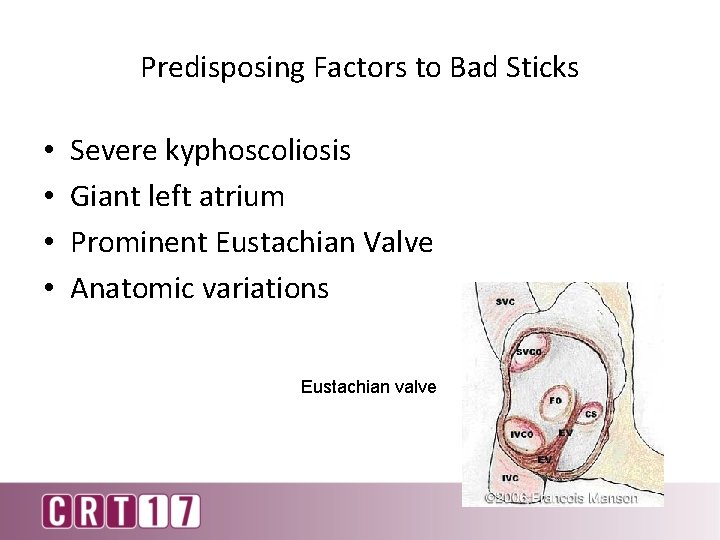

Predisposing Factors to Bad Sticks • • Severe kyphoscoliosis Giant left atrium Prominent Eustachian Valve Anatomic variations Eustachian valve